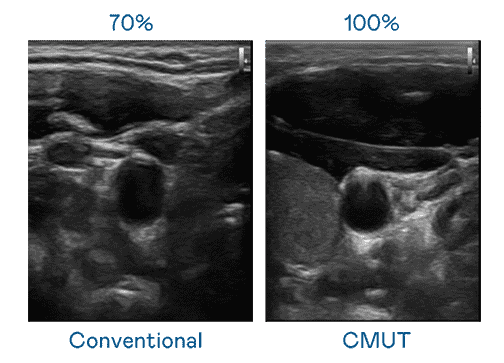

CMUT 技术是一种用电容式微机电元件来产生超音波讯号的技术。。。与传统 PZT 压电式技术相比,,CMUT 频宽增加 30%,,,更宽频的超音波讯号让影像解析度大幅提升,,是实现高影像品质医疗超音波扫描、、、促进精准医疗发展的关键技术。。。。

大频宽带来超清晰影像

超音波影像的解析度高低,,首先取决于探头能发出的讯号频宽。。。。www.z6.com CMUT 可提供高清晰的超音波讯号,,提供高频宽、、、高灵敏度、、、、影像纹理细节更高的超音波影像,,,协助医护人员缩短影像判读时间及利用精准的医疗影像进行诊断。。